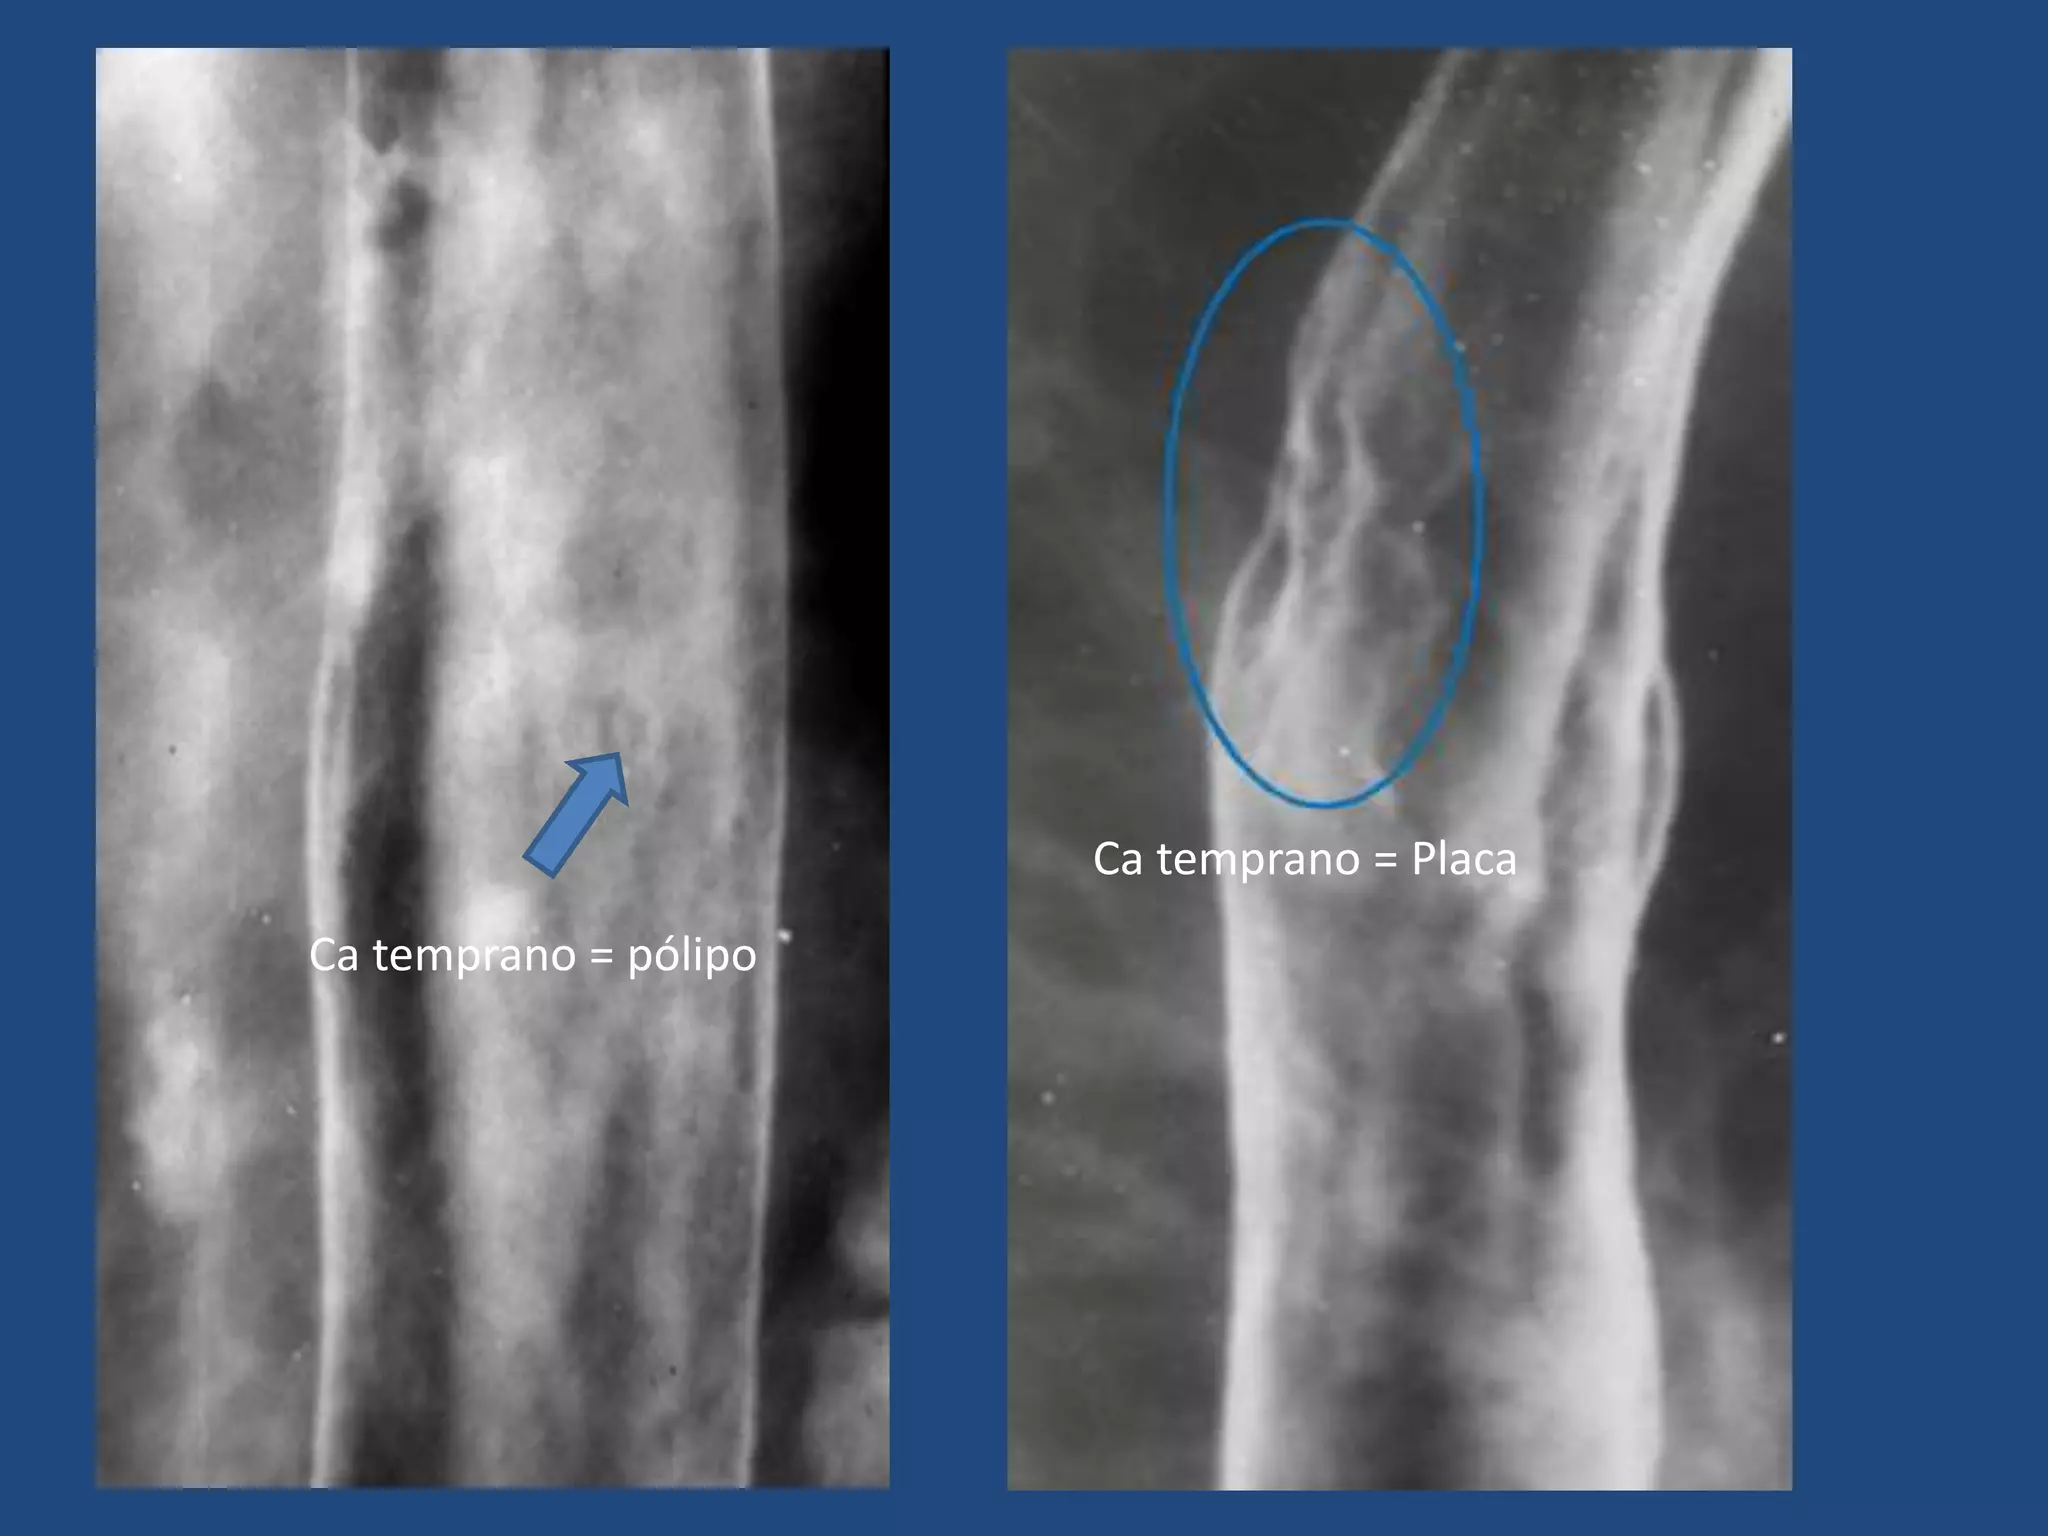

ESÓFAGO: TUMORES MALIGNOS

Hallazgos tempranos:

- Inicia como un pólipo aplando sésil o placa

aplanada sobre la pared.

- Pequeña ulcera central

- Rigidez de la pared (difícil dx dif con lesiones

benignas).

Placa aplanada Ulceración

Ca temprano = pólipo

Ca temprano = Placa